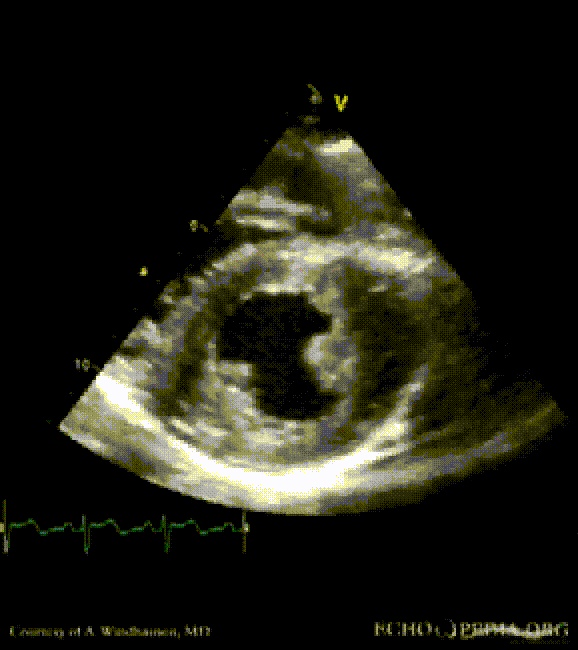

Severe Hypertrophic Cardiomyopathy (HCM)

Case description: Severe Hypertrophic Cardiomyopathy (HCM)

Courtesy of: A. Windhausen, AMC, The Netherlands

MM0001.gif MM0002.gif

A2CH view A4CH view